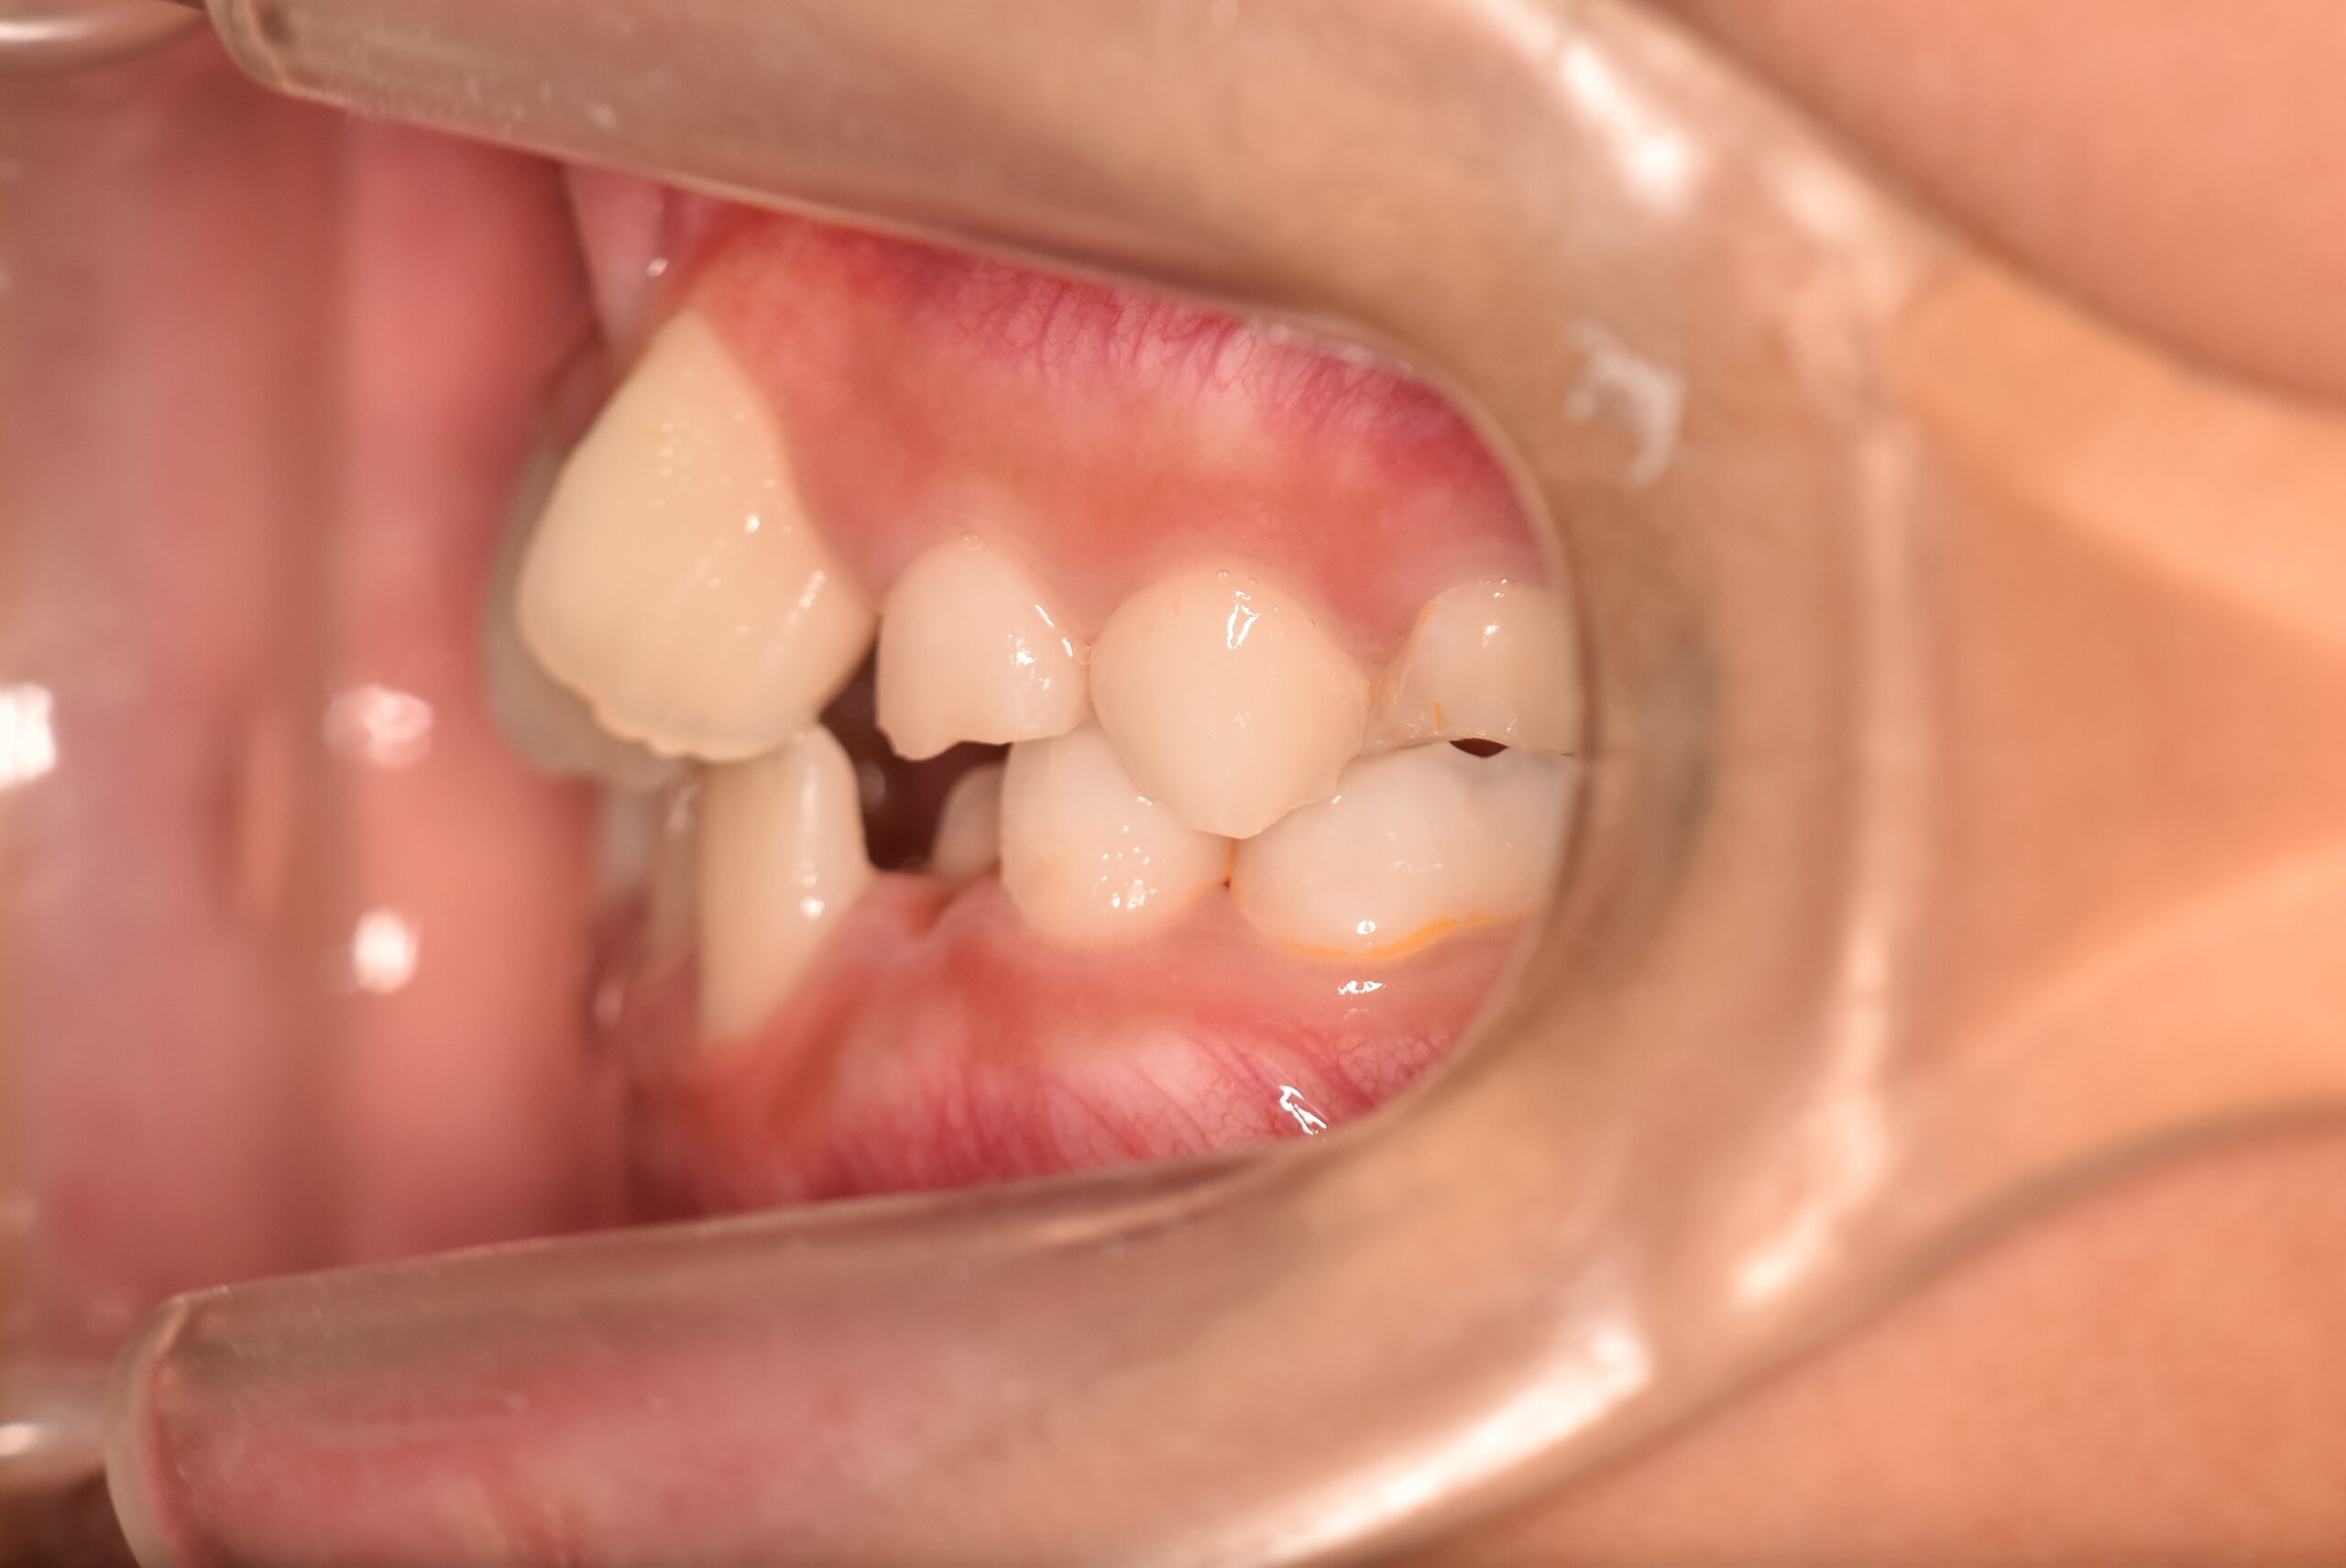

| 初診時 年齢 |

9歳3ヶ月 | 性 別 | 男性 |

|---|---|---|---|

| 治療期間 | 1年6ヶ月 | 費 用 | 矯正施術料:800,000円 調整料:4,000円/月 |

| 治療内容の詳細 | 初診時9歳3ヶ月の男児で、前歯が磨きにくく虫歯になりやすいことを気にされ来院されました。 検査の結果、前歯部叢生を伴うアングルⅠ級不正咬合と診断しました。 治療としてはマウスピース矯正(インビザラインファースト)で配列を行い、上下顎の側方拡大により永久歯の萌出スペースを確保しました。 治療期間は、1年6ヶ月でした。 今後、永久歯(側方歯)の生え変わりまで経過観察を行います。 |